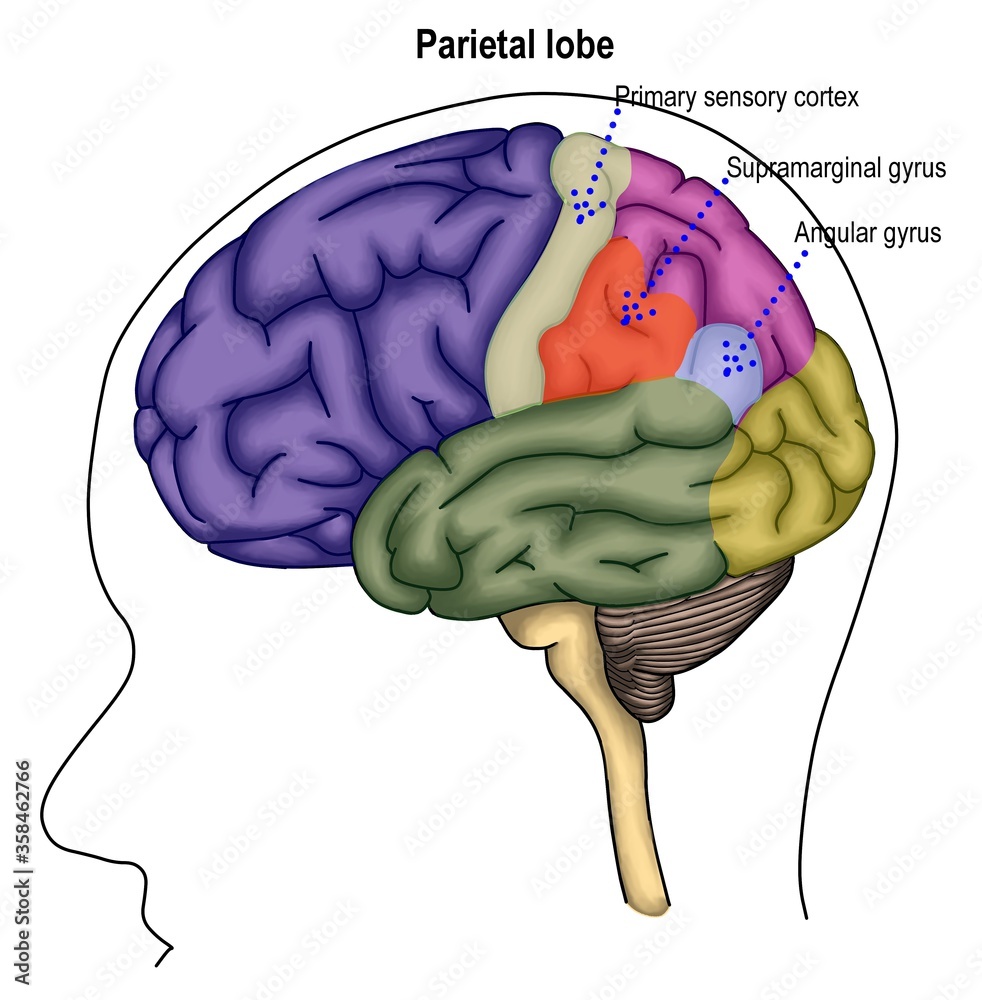

Супрамаргинальная извилина: Функции и Исследования